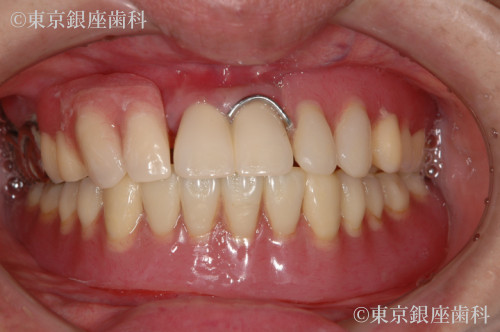

過去のインプラントで十分な結果が得られず再チャレンジし噛む機能を取り戻した60歳代女性の症例

Before

以前のインプラントが不十分で再治療を希望。下顎から先にインプラント、上顎洞炎治療後に上顎も実施。難症例ながら最終的に噛める状態を獲得。

上下ワンデイインプラント(再チャレンジ症例)